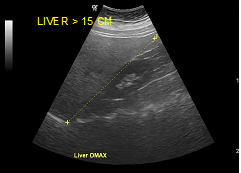

The fatty infiltration of the liver is shown on ultrasound with significantly increased echogenicity "bright liver", in comparison with the right kidney cortex (Figure 1). Normally, the liver and the renal cortex have similar echogenicity, relative to the parenchyma of the pancreas and the spleen. The maximum diameter of the liver in the midclavicular line (MCL) was increased, right lobe>15 cm (Figure 5). Also significant features are the absence of mass effect on intrahepatic vasculature (Figure 6) as well as the poor visualization of the deep parts of the liver (Figure 7), due to decreased permeability of the acoustic beam. A focal or diffuse morphology has been shown to increase the echogenicity of the fatty liver. Differential diagnosis is caused by focal fat infiltration (Figure 8), which has a geographic distribution. In this case, hypoechoic areas correspond to normal hepatic parenchyma on fatty infiltration sites, whereas, normal parenchyma islets can easily be identified due to their typical positions, in front of the right branch of the portal vein, its division, around the area of the gallbladder and the caudate lobe.9−13

Figure 5 Dmax right lobe>15 cm.